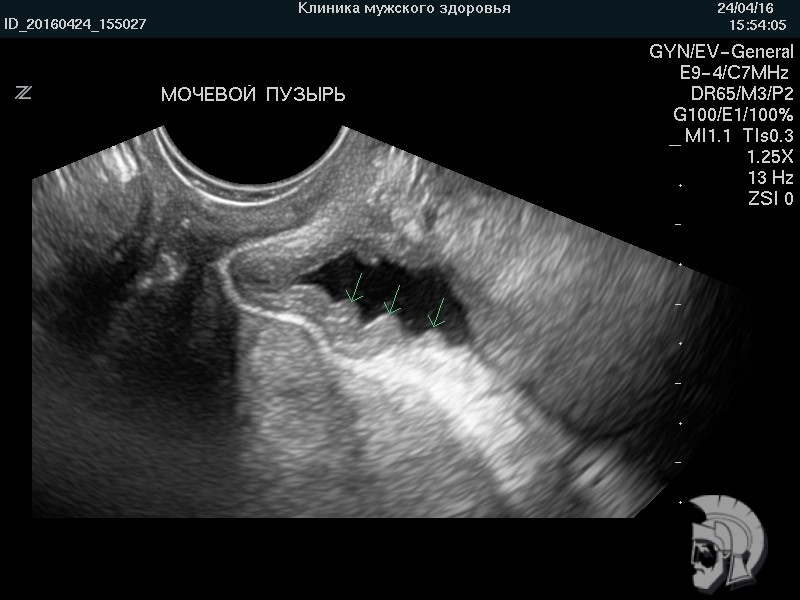

| Фото мочевого пузыря нетугого наполнения. Складки слизистой оболочки мочевого пузыря |

Обратите внимание на совершенное качество фотографий, свидетельствующих об экспертном классе аппаратов УЗИ.

Использование ультразвуковых аппаратов экспертного класса с режимами энергетического ДОППЛЕРа и цветового допплера позволяет врачам Курортной клиники мужского здоровья выявлять патологические изменения на ранних этапах их формирования и решать диагностические задачи высшей степени сложности.